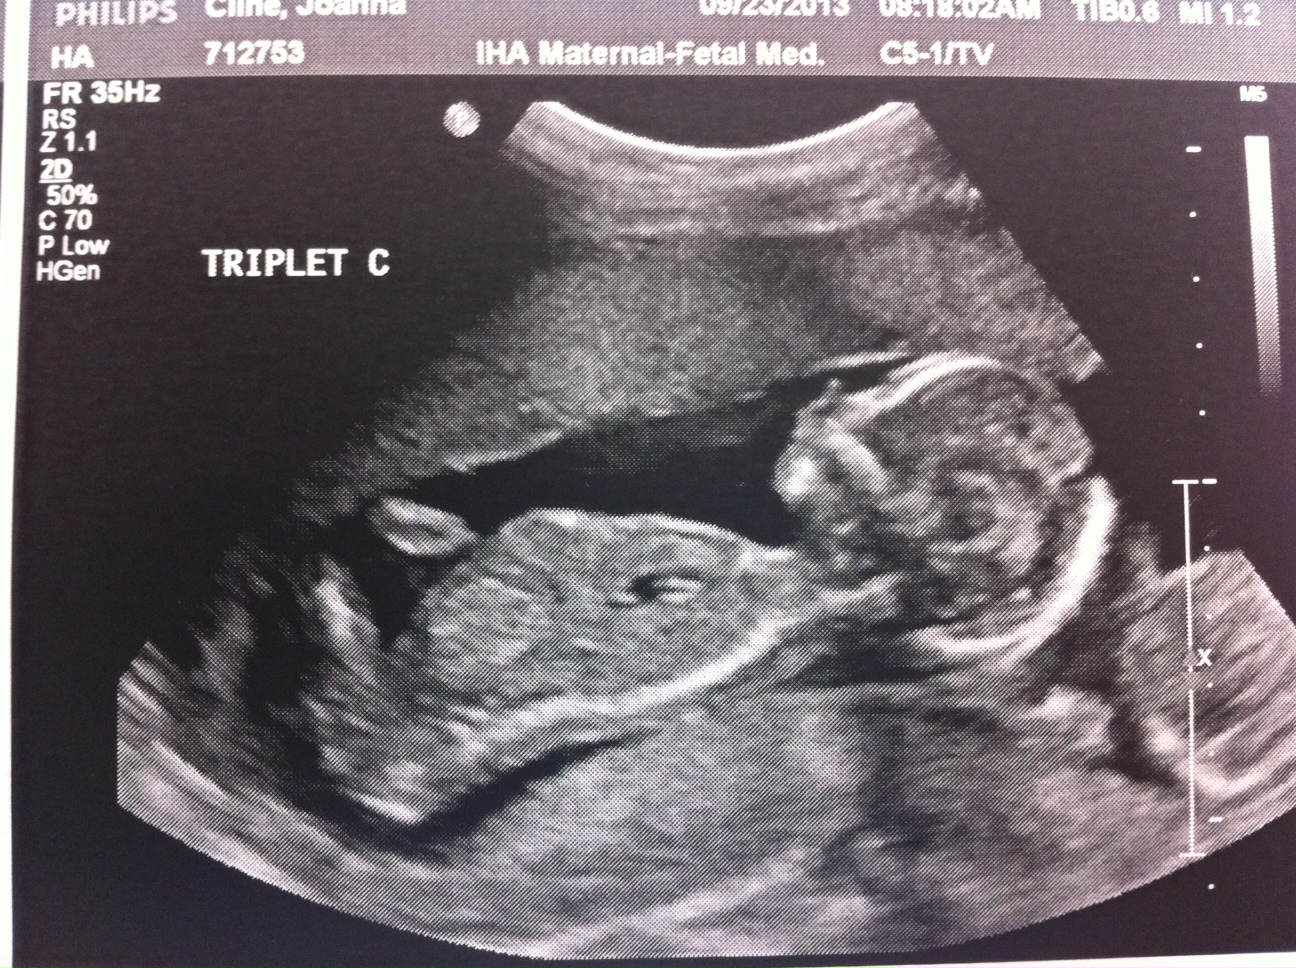

Baby C – is a BOY!

A is 170 grams, B is 175 grams and C is 178 grams so they’re all measuring well. Grow, grow, grow!